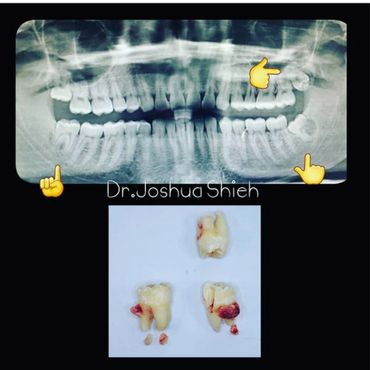

If the tooth is planned for extraction, an x-ray of the area will be taken to plan for the type of extraction.

A surgical extraction is a more complex procedure. It is used if a tooth may have broken off at the gum line or has not come into the mouth yet. Surgical extractions are commonly performed by general dentists or oral surgeons depending on the case. Sometimes it’s necessary to remove some of the bone around the tooth or to cut the tooth in half in order to extract it. For surgical extractions, patients receive local anesthetic. A suture is usually required to control bleeding and facilitate healing.

Wisdom teeth are the third set of human molars. Unfortunately, in some cases, those teeth are impacted fully or partially in bone or soft tissue and cannot erupt causing pain, discomfort and swelling. Additionally, most people have difficulty accessing these teeth during brushing or flossing causing accelerated decay and gum problems. Wisdom teeth have also been notorious for causing crowding, improper bites and pressure when they start erupting. The arrival of these late-breaking teeth can cause trouble as they are often impacted (trapped in the jawbone) because there is not enough room for them in the mouth. Our jaws are a lot smaller than those of our early human ancestors, who needed bigger jaws and more teeth for the type of food they chewed. In most people, wisdom teeth can do more harm than good and we often recommend their removal.

It can take a long time for wisdom teeth to erupt and you may not even notice the harmful effects in your mouth until you experience sudden and severe discomfort. Cramped for room, impacted wisdom teeth grow out at odd angles or remain trapped below the gums. Adjacent teeth can become prone to decay because of the unfavourable position of the wisdom teeth.